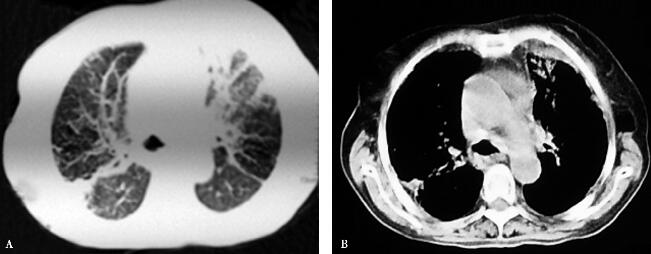

5.胸部影像学:

双肺多发条索状及网状阴影(图1)。

图1

【临床分析】

重要的检查结果有三项:①白细胞计数、中性粒细胞百分比均增高;②胸部影像学示双肺多发间质性病变;③动脉血氧分压降低。结合患者的病史和体格检查结果,进一步支持感染性疾病,但患者肺部查体有Velcro啰音,肺功能提示弥散功能异常,提示有间质性肺疾病,综上结果提示间质性肺疾病合并有肺部感染。患者发病以来反复抗感染治疗,曾应用广谱抗生素治疗,效果均较差,考虑可能因未能覆盖病原体或基础疾病未系统治疗。

无明显临床症状,动脉血气分析(未吸氧):pH 7.41,PaO2 78mmHg,PaCO2 40mmHg。胸部CT病变明显吸收。

病情稳定,胸部CT病变明显吸收。